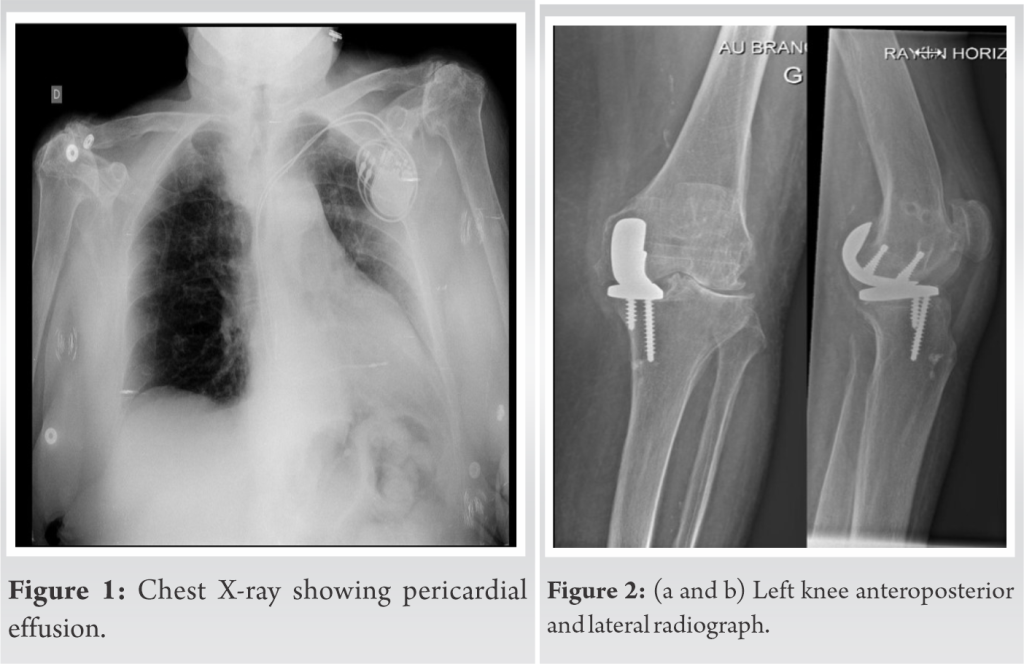

From jocr.co.in

Septic Metallosis after Knee Replacement A Case Trunnionosis Vs Metallosis Higher co/cr ratios have been more closely linked to. The main question is what is trunnionosis and what do we need to know as a surgeon. It is defined as wear or corrosion at the trunnion, the. Find out the risk factors, diagnosis,. Learn about the risk factors, pathophysiology, presentation,. It generates metal debris and causes adverse reaction to metal. Trunnionosis Vs Metallosis.

Oxidized Zirconium Bearing Surface Failure in Total Knee Arthroplasty Trunnionosis Vs Metallosis It generates metal debris and causes adverse reaction to metal debris (armd), which can lead to revision surgery. Find out the risk factors, diagnosis,. Specifically, we present the literature on (1) the effect of femoral head size on trunnionosis, (2) the effect of trunnion design on. The main question is what is trunnionosis and what do we need to know. Trunnionosis Vs Metallosis.